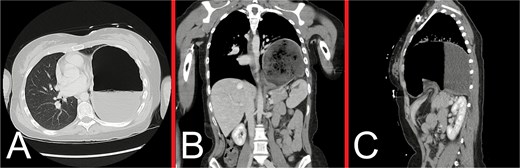

On admission day three, she deteriorated acutely with worsening pain and dyspnoea, desaturations and haemodynamic instability, warranting new oxygen and inotropic support. An urgent bedside CXR showed a new, left tension pneumothorax (Fig. 3). Urgent beside decompression with intercostal catheter (ICC) insertion yielded large-volume gastric content output (Fig. 3). A repeat CT chest demonstrated a new, left hydropneumothorax, raising suspicion for gastric perforation and evolving mediastinitis (Fig. 4).

(A) Urgent bedside CXR demonstrating a new, large, left pneumothorax with significant rightward mediastinal shift, consistent with a tension pneumothorax. (B) Anteroposterior CXR following insertion of a left ICC via an anterior approach, showing restoration of the mediastinal structures to the midline, improved aeration of the right lung and near-complete collapse of the left lung. Obliteration of the left hemidiaphragm outline, left hydropneumothorax, and gastric herniation into the left hemithorax are also demonstrated.